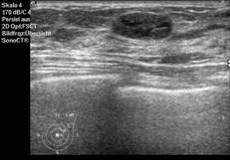

Die Mammasonografie erlaubt die Darstellung von zystischen und soliden Herdbefunden, die anhand verschiedener Kriterien hinsichtlich Gutartigkeit oder Bösartigkeit weiter charakterisiert werden. Hierzu werden die Form, Begrenzung, Ausrichtung und Binnenstrukturen von Herdbefunden sowie die umgebenden Gewebestrukturen beurteilt. Zusammen mit der farbkodierten Dopplersonografie (Darstellung von kleinen Blutgefäßen) ermöglicht die Mammasonografie eine Differenzierung zwischen gutartigen und bösartigen Veränderungen. Mit Hilfe moderner Ultraschallgeräte lassen sich Herdbefunde ab einer Größe von 5mm nachweisen.

Wesentliche Voraussetzungen für eine qualitativ hochwertige Mammasonografie sind moderne Ultraschallgeräte mit speziell für die Brust konzipierten linearen und hochauflösenden Schallköpfen mit hohen Frequenzen (› 7,5 MHz) und damit hoher räumlicher Auflösung. An unserem Institut steht für die Mammasonografie ein solches Gerät zur Verfügung (HDI 5000, Phillips).